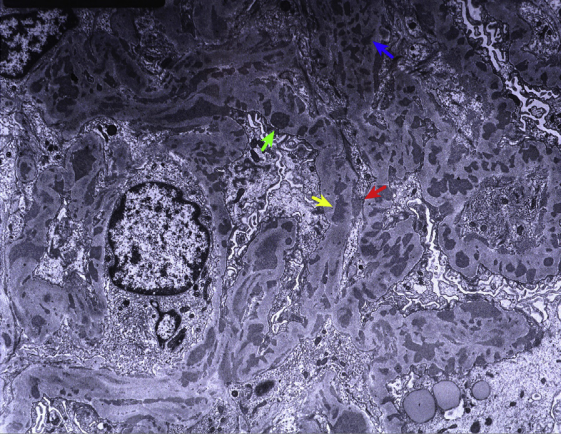

狼疮型肾炎Ⅴ型+Ⅲ型(膜性+局灶性LN),沿肾小球基底膜上有钉突(红色、蓝色箭头),双轨和早期新月体形成(银染)。